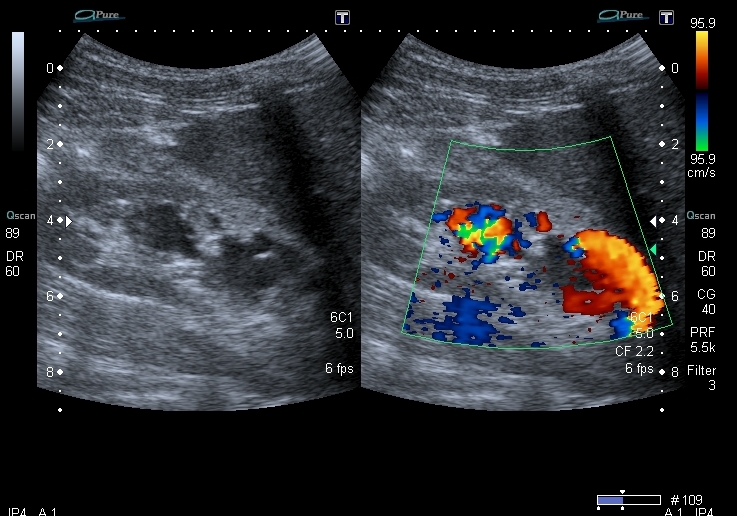

Юноша 17 лет , с 5 лет наблюдается по поводу хронического гломерулонефрита, 2 раза литотрипсия слева. При плановом УЗИ исследовании - диффузные изменения паренхимы почек, пиелоэктазия слева, небольшая киста в левой почке и группа полостных образований в синусе правой почки.

К сожалению так и не наладил архивацию видео в аппарате, взамен убиваю интригу (почти) и прикрепляю скан с ЦДК

После всех этих находок я предположил наличие сосудистых мальформаций правой почки в виде артерио- венозных соустий. К сожалению на УЗИ не смог разобраться с происхождением крупного артериального сосуда, который был атипично расположен по передне -наружной поверхности правой почки

В связи с этим порекомендовал провести ренальную ангиографию, что и было выполнено

Протокол ДСА:брюшная аорта не расширена. Почечные артерии - слева без изменений. Справа - рядом с основной неизменённой почечной артерией - дополнительная артерия с просветом 6 мм, подходящая к нижнему полюсу почки, кровоснабжает клубок патологически изменённых сосудов с ускоренным кровотоком и сбросом в расширенную почечную вену и далее в НПВ. Заключение: артерио - венозная мальформация нижнего полюса правой почки.